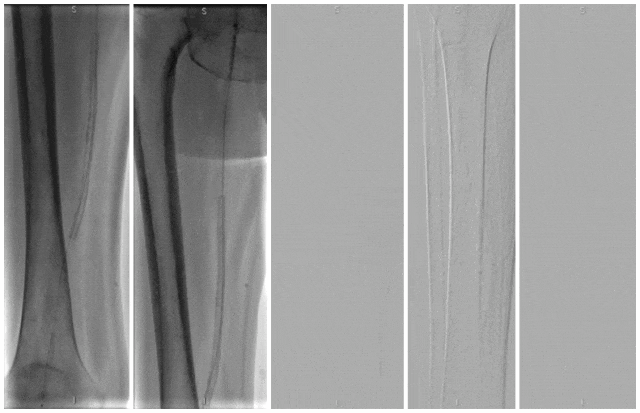

血栓闭塞性脉管炎(TAO)的激光治疗研究

★ 研究设计与方法

本研究为单中心回顾性分析,比较激光辅助球囊扩张与单纯球囊扩张治疗TAO膝下动脉病变的效果。

★手术过程

术中顺行穿刺到达狭窄或闭塞病变段附近,在病变段近端予硝酸甘油/罂粟碱扩血管及尿激酶溶栓,导丝通过狭窄或闭塞病变段到达远端流出道后,在膝下动脉使用准分子激光系统(CVX-300 准分子激光系统)减容。采用0.9mm-2.0mmELCA激光导管,以小于 0.5-1 毫米/秒的速度缓慢通过病变段,激光能量30-60mJ/mm2,频率25-80Hz,重复2-3次。在获得管腔后,使用1.5mm-3.0 mm球囊进行球囊扩张。

当ELCA导管无法通过闭塞病变段时,将尝试使用1.5 mm球囊预扩张。当激光导管和球囊均未能通过动脉时,认为激光辅助球囊扩张治疗失败,仅予扩血管、溶栓缓解下肢缺血后结束手术。

图:激光辅助血管成形术干预的DSA和IVUS成像。

(A) 基线血管造影; (B) 准分子激光减容; (C) 球囊扩张; (D)术后血管造影

共回顾性地纳入接受过激光辅助球囊扩张治疗52人,纳入单独行球囊扩张治疗158人。

激光辅助球囊扩张组中37例成功接受激光减容和球囊扩张联合治疗(技术成功率为71.15%),而球囊扩张组技术成功率为65.82%。

成功进行激光辅助球囊扩张治疗的患者和未成功进行该治疗的患者在病变长度和靶动脉分布方面没有显着差异。

成功接受激光辅助球囊扩张治疗的患者平均最大能量为52.84±4.00 mJ/mm2 (范围为45-55 mJ/mm2 ),平均最大频率为62.03±4.16Hz(范围为50-65Hz)。治疗后,IVUS测量的靶血管壁最小厚度为1.10±0.29mm(范围为0.52-1.53mm)。

无动脉穿孔、远端动脉栓塞等不良事件发生。